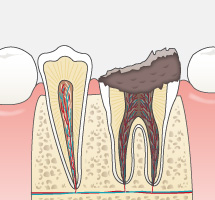

今まで一般的に行われていたむし歯治療は、痛くなったら歯医者に行き治療する、という流れの繰り返しではなかったでしょうか?痛くなってから、むし歯が進行してからの治療は削る・抜歯することが多くなり、徐々に自分自身の天然の歯は「詰め物」や「被せ物」さらには「インプラント」や「入れ歯」になっていきます。天然歯は削ってしまうと二度と元には戻りません。

可能な限りご自身の歯で食事を楽しんだり、話したりして健康な生活を送っていただきたい。だからこそ当院ではできるだけ歯を残す治療をおこないます。単なる対症療法の“削って詰める”ではなく、病原菌の除去をしてからMI(Minimal Intervention:できるかぎり削らず、削っても最小の範囲で)の考えのもと原因療法を施し、治療後はむし歯の再発や新たなむし歯の発生を予防することを目標としています。